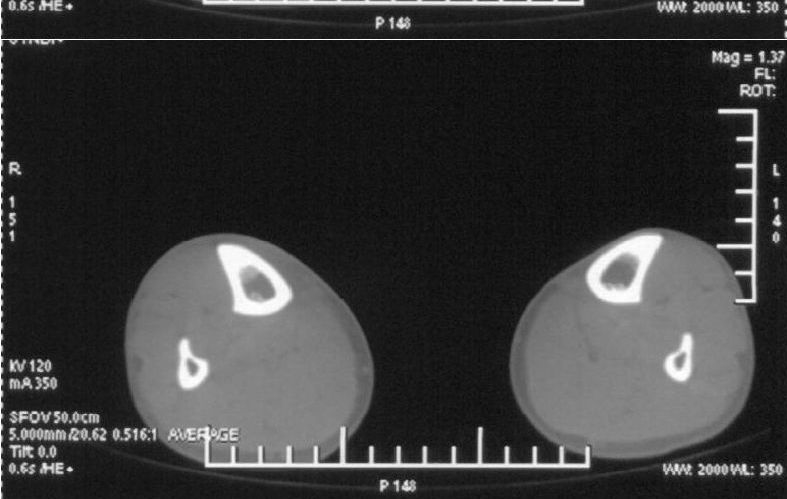

男,42岁。4个月前钢筋钝伤右侧小腿部,当时因无明显外伤,未引起重视。一周后因受伤腿部疼痛,发现肿胀,随后到当地医院进行检查(2008年4月16日)。因未发现骨质异常未引起重视,仅仅进行口服抗生素治疗处理。经过一段时间治疗但未见明显治疗效果在5月29日又进行x线检查,发现有胫骨密度上段密度增高,又进行抗炎治疗,仍未见效果。又在7月3日进行x线检查,仍然报告有胫骨上端密度增高,并建议ct检查。以下是相关检查结果:

该患者到某三级医院进行会诊,并重新作了平片检查,认为畸形性行骨炎:

髓腔密度呈絮状增高,胫骨上端内侧可见层状骨膜反应,考虑骨髓炎.

髓腔密度呈絮状增高,胫骨上端内侧可见层状骨膜反应,肌间隙模糊,考虑骨髓炎.